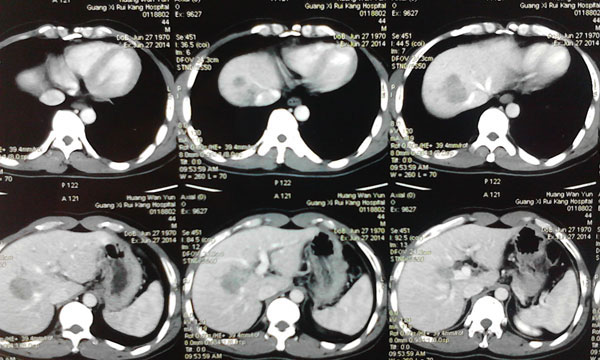

7月6日,卫生部肝胆肠中心的李年丰教授和我院肝胆外科主任韦杨年副教授及其团队主刀为患者手术。术中探查发现肿瘤位于肝脏ⅦⅧ段,大小约有8.0cm×5.0cm×5.0cm,左肝轻度硬化。在仔细探查后,韦主任为他施行了腹腔镜下门静脉右支结扎+肝脏离断术+胆囊切除术。

术后,黄先生被送回病房修养。在医护人员的精心治疗和护理下,患者病情稳定,仅有低热及轻度的疼痛,肝功能稳定。在术后第七天, CT检查发现左肝残肝增生明显,残肝体积已经达到右半肝切除的要求。

7月16日,韦杨年主任再次主刀,为黄先生施行右半肝切除术。手术非常顺利,术中无需阻断第一肝门,最大限度地保护了左肝残肝的功能。经过两次手术,成功切除右半肝,剖示肝脏肿瘤大小约8.0cm×5.0cm×5.0cm,肿瘤病理结果为:肝细胞肝癌。

第一次术后复查CT